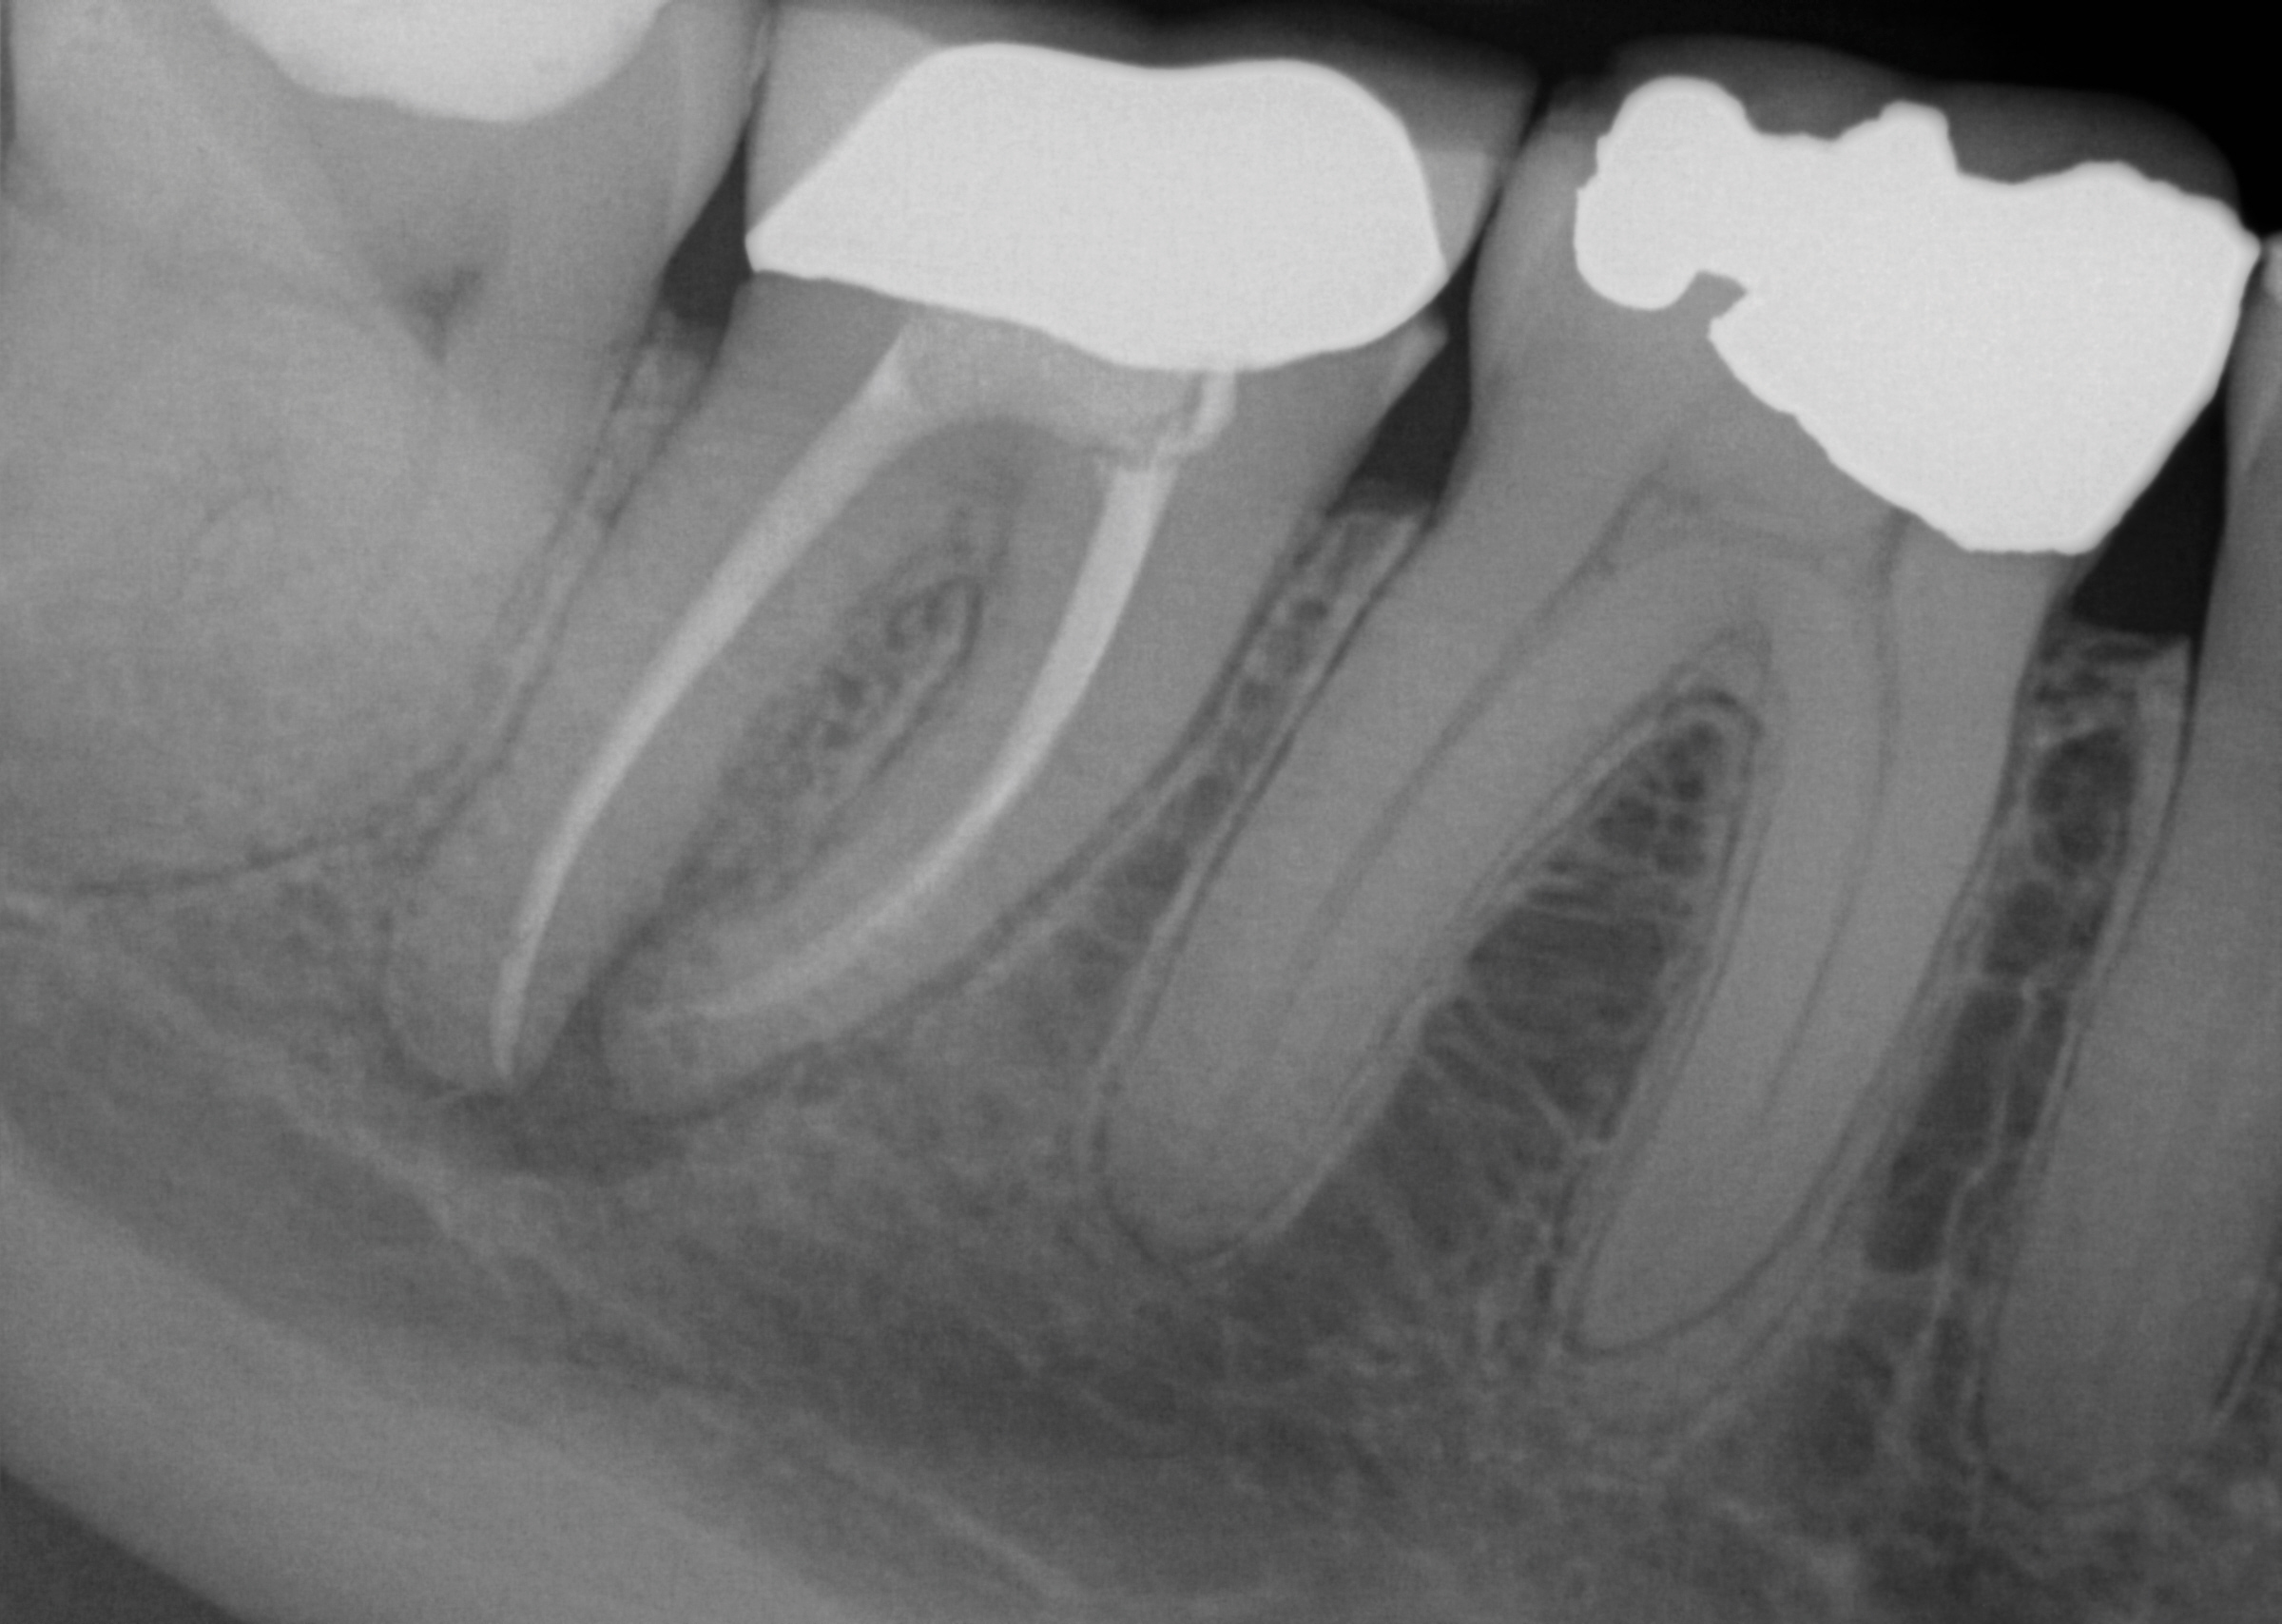

Before extracting a mandibular molar or premolar in preparation for an implant, assess the location of their roots in relation to the IAN and mental nerve, because if a nerve is juxtaposed to the roots of teeth, tooth removal has the potential to induce nerve damage. Furthermore, caution should be exercised when debriding large periapical radiolucencies, because these lesions may communicate with a nerve canal (Figure 3 and Figure 4).

Fig 3. A patient presented with intense pain in tooth No. 31. A periapical radiograph demonstrated acute apical periodontitis. It was not possible to identify the extent of the periapical lesion with respect to the inferior alveolar canal.

Figure 3

Fig 4. A CT scan was obtained. The scan demonstrated the proximity of the apical lesion to the canal. With proper preoperative planning and imaging, the tooth was successfully removed and the granulomatous tissue carefully debrided without inducing any altered nerve sensation.

Figure 4